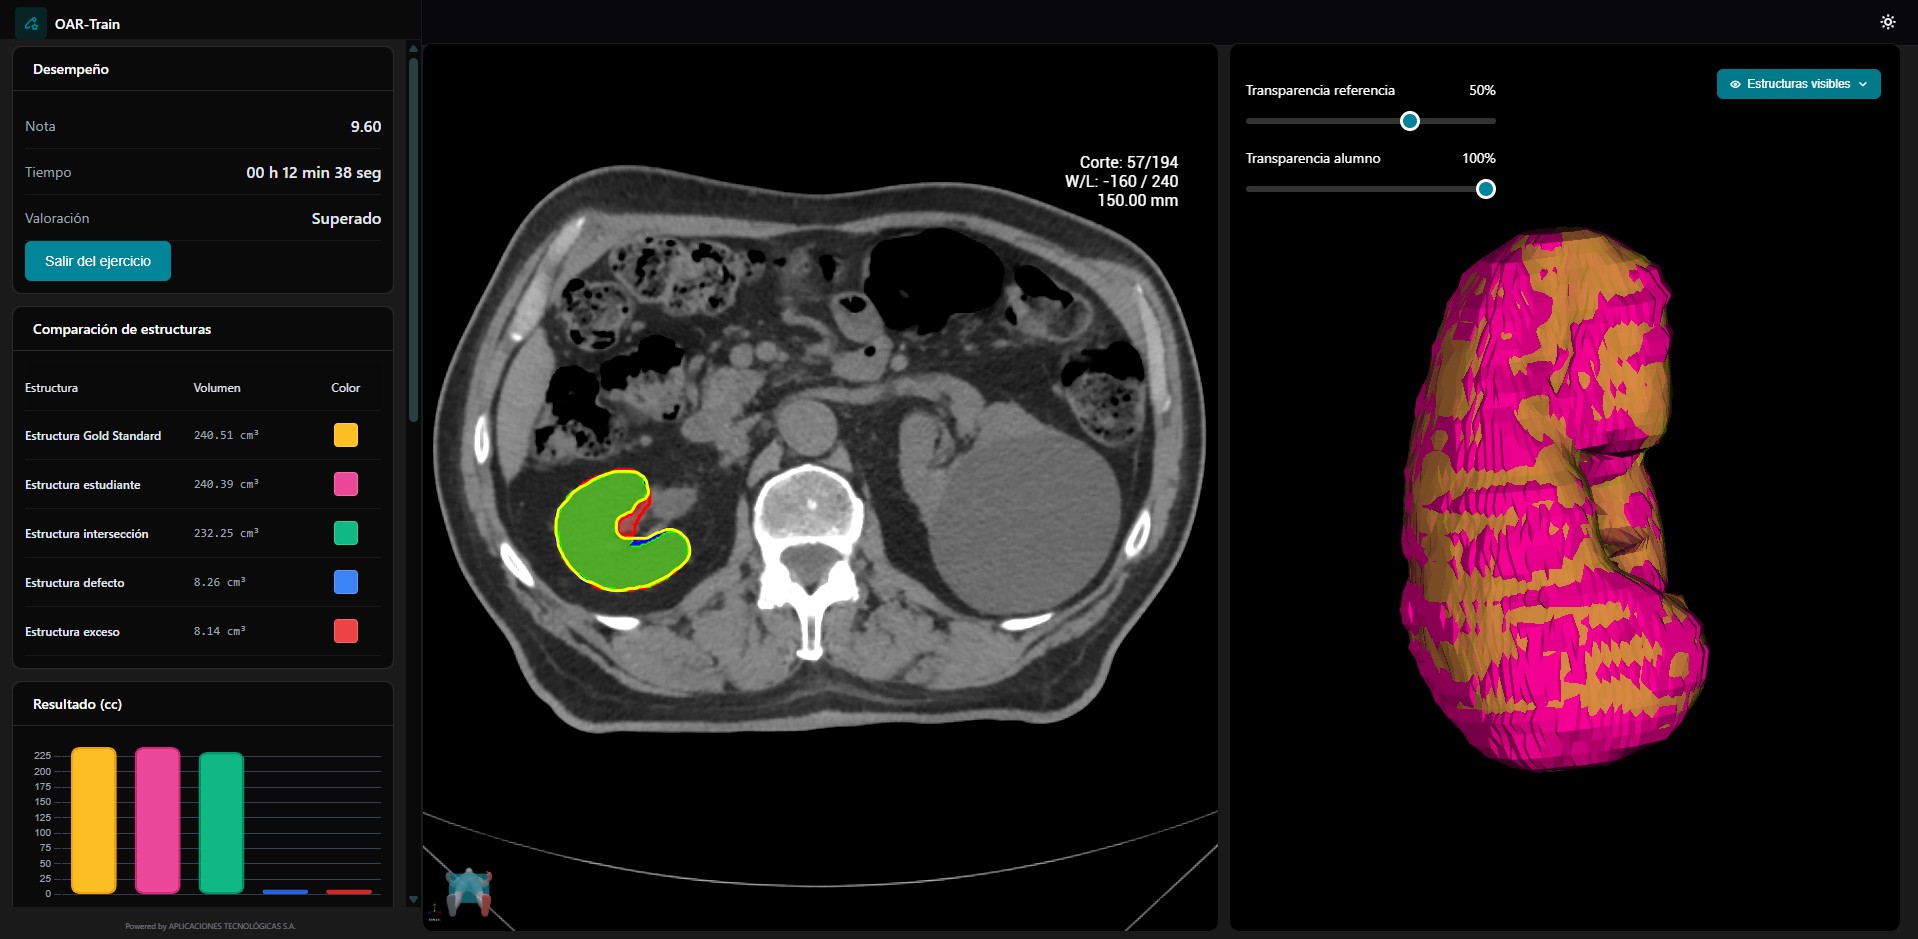

OAR-Train

Preservar lo sano, tratar con precisión

Curso de delimitación de órganos de riesgo dirigido a técnicos de dosimetría

Contorneo para técnicos de dosimetría

Herramienta formativa de aprendizaje de la correcta delimitación de órganos de riesgo (OAR). Engloba las distintas regiones anatómicas.

- Cada módulo se dedica a una región anatómica.

- Los ejercicios incluyen las imágenes de TC con un editor para dibujar los contornos.

- El ejercicio práctico se evalúa de modo automático a través de un algoritmo de comparación.